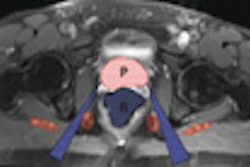

![]() |

| Figure 2. Axial T2-weighted MR image of the pelvis shows increased signal within the soft tissue adjacent to the right ischial tuberosity (white arrows). |